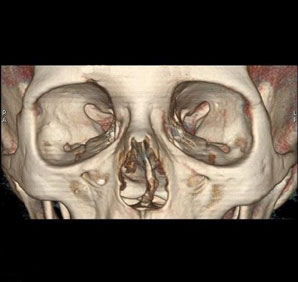

Tomografía computarizada Órbitas

< Volver a "Tomografía Computarizada (TC) con Inteligencia artificial"Está indicado para el estudio de los globos oculares o de los huesos de las órbitas (traumatismos).